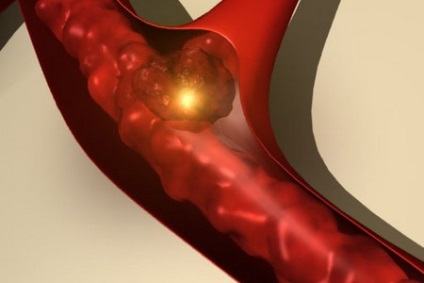

Az öregek, ágynyugalom, alkothatnak vérrögök

Ez történt a vakolat verzió, ha nem lehet megvenni egy pár szintetikus anyagból készült. Az ágynyugalom - megpróbáltatás az idősek (az emberek több mint 75 év). Korlátozása motor üzemmódban, körülbelül egy hónap, még (a legjobb esetben) vezet súlyos szövődmények, életveszélyes. Ezek a következők:

- Thrombophlebitis.

Lassítása véráramlás vénákban, különösen az alsó végtagok, ágynyugalom az idősek gyorsan növekedéséhez vezet a véralvadásban a vaszkuláris lumen, gyulladás a véna fal. Alakult vérrögök bejutni a rendszerbe a vena cava inferior szíven a pulmonális artériába, ami a tromboembóliás feltétellel, hogy képes túlélni, nem minden idős ember. Fekvést az idősek veszélyes csökkenése mellkasi mozgások pangásos tüdőgyulladás, ami a leggyakoribb halálok idősek csípőtáji törések (20%).